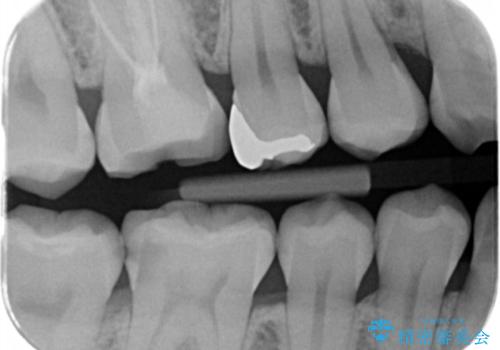

見た目ではわかりにくい虫歯ですが、レントゲン画像でははっきりと写っていました。

まだ虫歯の大きさが小さいためインレーでの修復処置を行います。